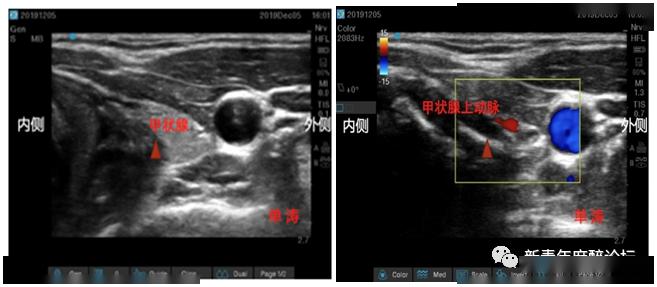

超声专题超声引导喉上神经阻滞的临床实战思维

神经两个重要的分支,但是由于这两个分支的复杂走行过程,超声并不能